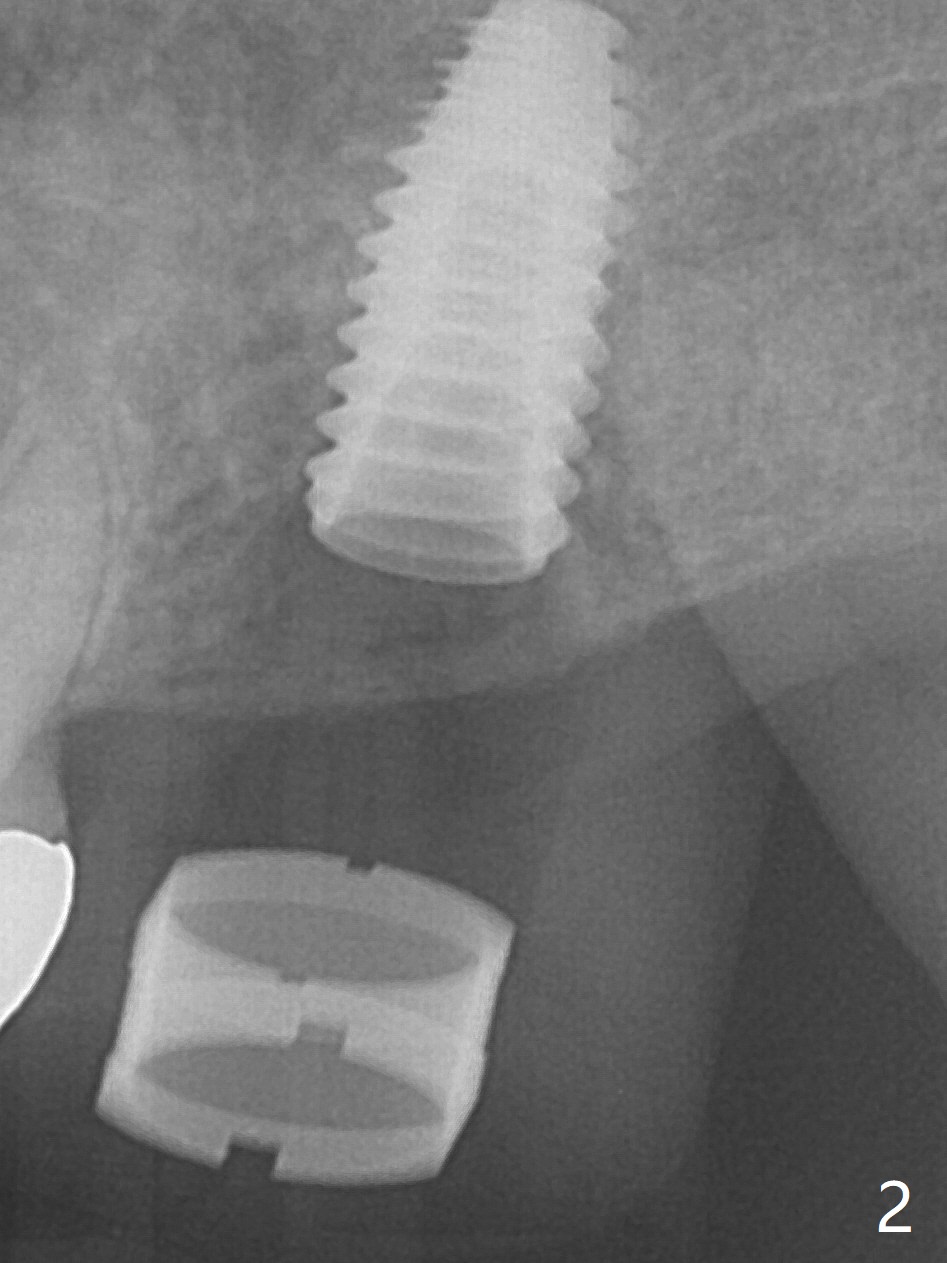

After extraction at #15 with 9 mm offset, a 12 mm bone trimmer is used to create a dimple in the septum. When a 4x7.3 mm drill is done according to drill sequence, initial osteotomy has no palatal wall. A 4.5x10 mm dummy implant cannot engage for sinus lift. DIO Sinus Approaching drill cannot enter IS green metal sleeve. When a 4x8.5 mm drill is finished, the sinus floor is intact. This is not the case when a 2.2x10 mm drill is used. Water membrane lifter does not seal the osteotomy (palatal defect). The 4.5x10 mm dummy implant is used for sinus lift, followed by 2-3 Amalgam carriers of allograft lifted with the same implant (Fig.1,2). After 4x10 mm drill and 2-3 carriers of Vanilla graft, a 5x11.5 mm implant is placed >55 Ncm with immediate placement of a 5.7x4(2) mm abutment (Fig.3). With sticky bone and 2 pieces of PRF in the remaining socket, an immediate provisional is fabricated and seated. When the patient returns for impression nearly 6 months postop, she feels mild pain. In fact the temporary crown/abutment is loose and traps food underneath with the erythematous gingival cuff. A 5.7x4(3) mm abutment is placed and torqued without gap for impression (no temp); the implant threads are exposed distal (Fig.4 <). Retrospectively, the incompletely seated cemented abutment should be tightened ~ 1 month postop when the socket heals.